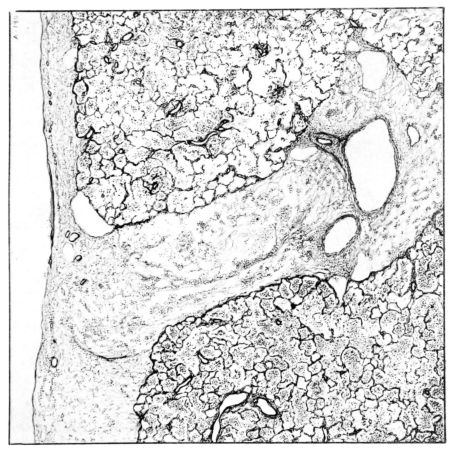

FIG. III. AUTOPSY NO. 90. DRAWING FROM A LESION OF THE TRACHEA (SOMEWHAT OLDER THAN THAT ILLUSTRATED IN FIGURE II). THE MUCOSA IS ENTIRELY LACKING. CONGESTION AND EDEMA ARE THE STRIKING FEATURES IN THE SUBMUCOSA. THE NECROTIZING PROCESS HAS EXTENDED INTO THE MUCUS GLANDS. THIS IS SHOWN IN THE LOWER PICTURE.

The changes are less marked, perhaps, in the trachea than in its finer ramifications. The mucosa is constantly more or less destroyed and large areas, usually focal, are entirely devoid of their epithelial covering. This is replaced by a sparse exudate, composed largely of red blood cells, mucus, a small amount of fibrin, and nuclear fragments (Fig. II). It may dip into the submucosa for a short distance, but usually these indentures are associated with the ducts of the mucous glands into which the inflammatory reaction extends. A more striking feature than the exudate, however, is the edema and the congestion of the submucosa. The loose areolar tissue of the submucosa is spread widely apart, and throughout it distended blood vessels are very conspicuous. Occasionally such a vessel is broken and actual hemorrhage appears in the submucosa. Occasionally, too, the inflammation extends down the duct to the mucous gland itself, and here, also, aplastic inflammatory reaction is evident, inasmuch as the acini now stain intensely red with the cells undifferentiated from each other and specked here and there by broken remains of the dead nuclei (Fig. III). After the disease has continued for a short period, even at the end of five or six days, some regeneration of the epithelial lining may be seen (3) (Fig. IV). But despite this, the acute picture persists, and there goes on, side by side, an attempted repair characterized by epithelial regeneration and the same evidence of acute change. Since the lesion is essentially a superficial one, scars or contractures of any extent are not encountered in the trachea, even in examples of the disease that have ended fatally only after many weeks.[4]